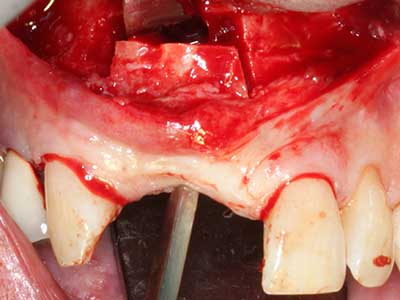

Abb. 3: Die basale Abtrennung des Blocks wird durch speziell abgewinkelte Aufsätze erleichtert.

Bei der Knochenblockentnahme zeigen sich weitere Vorteile für die Piezochirurgie: Neben der bereits beschriebenen hohen Präzision bei der Osteotomie stellt sich gerade die Verwendung der dünnen Sägespitzen als besonders materialschonend heraus. Bei der Verwendung insbesondere von Lindemannfräsen sind mit deutlich höheren Entnahmeverlusten durch die dickere Instrumentenspitze zu rechnen (Lakshmiganthan, Gokulanathan et al. 2012). Die insbesondere bei retromolar entnommenen Blocktransplantaten notwendige basale Abtrennung wird durch speziell hierfür vorgesehene rechtwinklige Sägen erleichtert, so dass die Piezochirurgie als präzises, übersichtliches und sicheres Verfahren zur retromolaren Knochenblockgewinnung angesehen wird (Happe 2007) (Abb. 1-12).